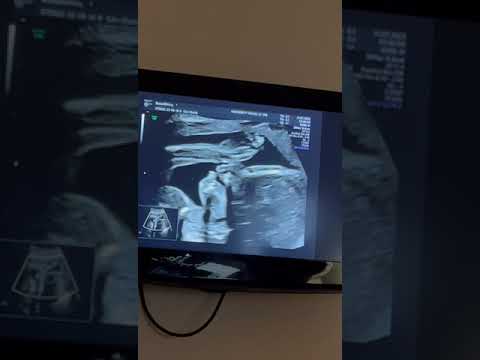

Как выглядит малыш на 20 неделе беременности: фото и УЗИ

На 20 неделе беременности малыш активно растет и развивается. В этой статье вы найдете подборку фото и УЗИ, а также полезные советы, которые помогут вам лучше понять, что происходит с вашим будущим ребенком на этом этапе.

На 20 неделе беременности ваш малыш уже размером с банан, и его движения становятся все более ощутимыми.

Как выглядит мальчик на всех скринингах узи.☺️

Двойня. Мальчики. УЗИ.

Чем занимается малыш @AlexsWorld23 в животе у мамы. УЗИ 20 неделя беременности, шевеления малыша

20. неделя беременности